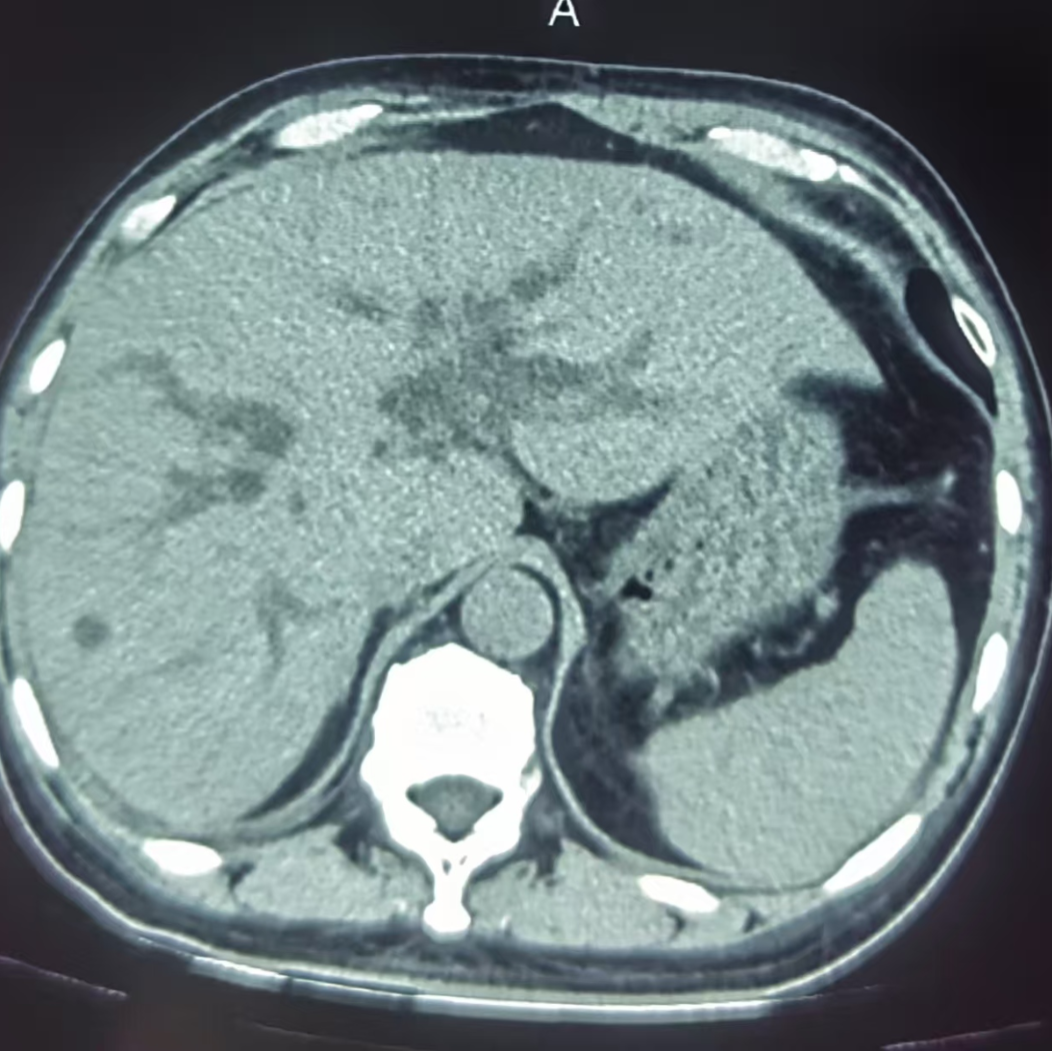

CT肝内胆管扩展 未见胆道结石